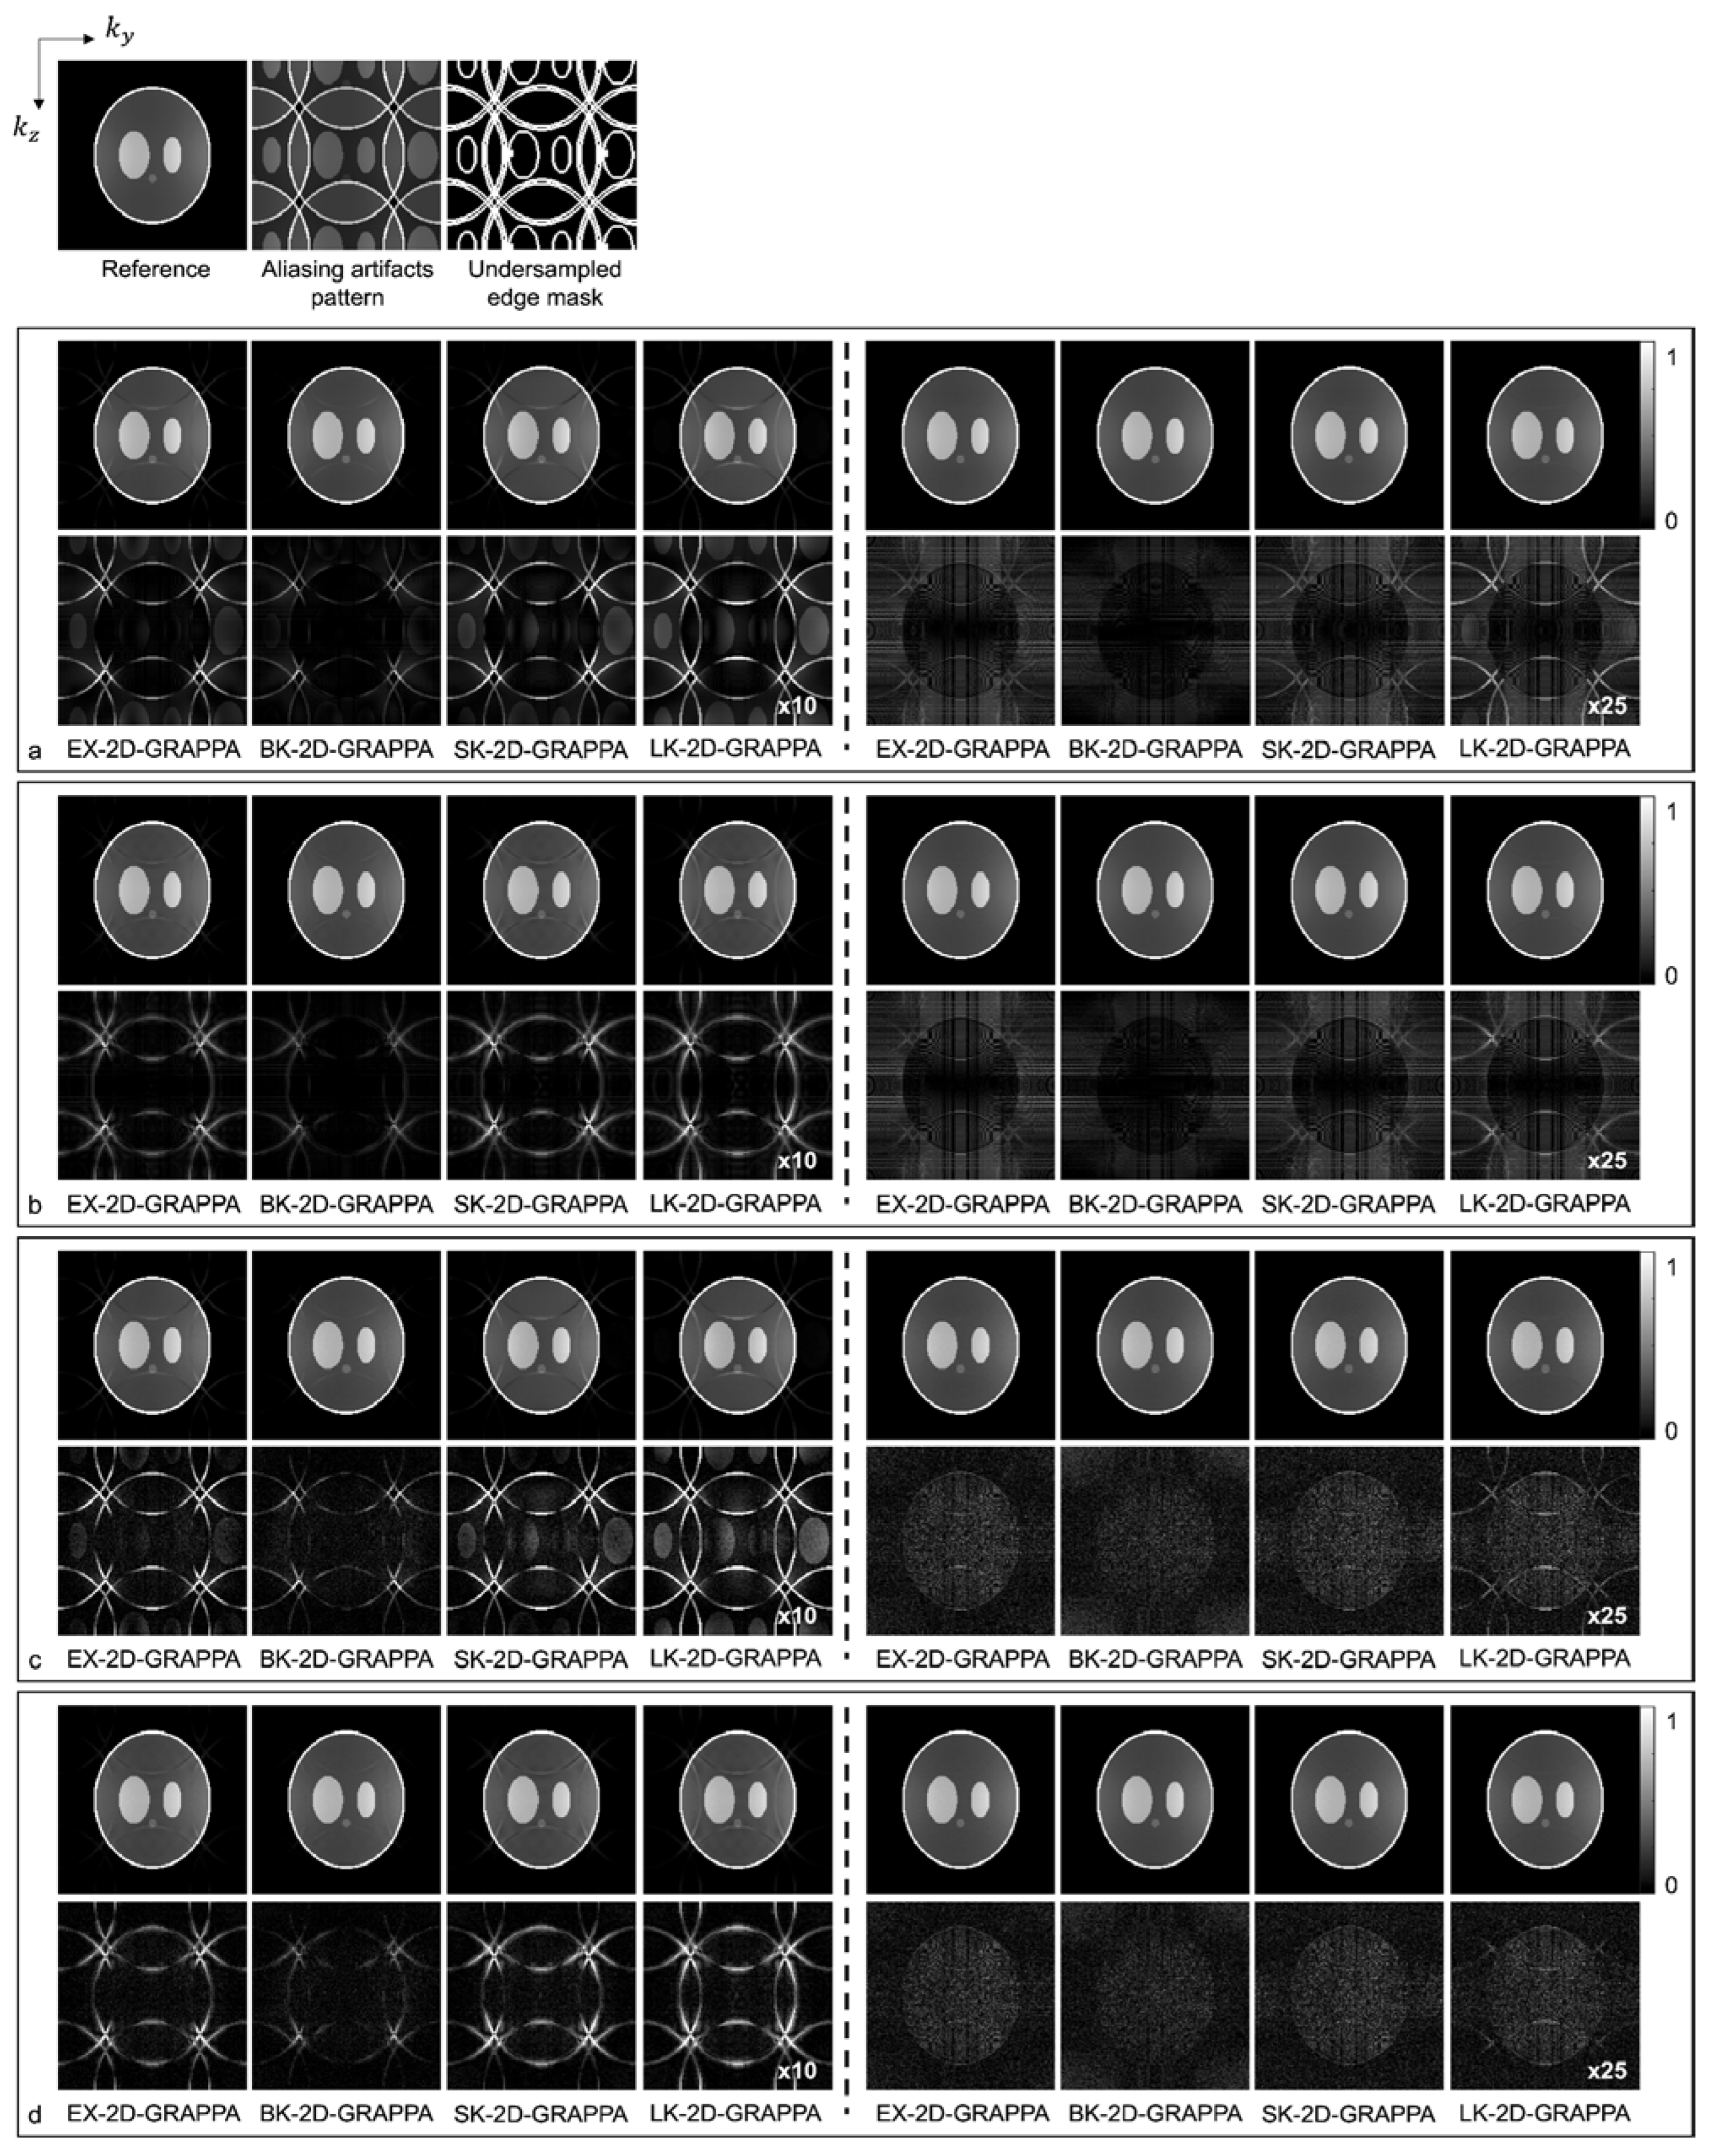

Figure 5.

The images reconstructed by different 2D-GRAPPA algorithms from (a,b) noise-free and (c,d) 30 db noise-added simulation data with AF = 4 (2 × 2). The 24 × 24 k-space reference lines were (a,c) excluded and (b,d) included for reconstruction. Columns 1–4: basis kernel. Columns 5–8: expanded kernel.

Images reconstructed from the simulated dataset with AF = 4 (Ry × Rz = 2 × 2) by different 2D-GRAPPA algorithms are presented in Figure 5. The images in Figure 5a,b were reconstructed from noise-free simulation data and the images in Figure 5c,d were reconstructed from noise-added simulation data. The BK-2D-GRAPPA algorithm showed less residual aliasing artifacts than any other 2D-GRAPPA algorithm, regardless of the presence of noise. The amount of residual aliasing artifacts decreased when the kernel was expanded. When the k-space reference data were included at the end of the reconstruction (for inverse Fourier transform), ringing and edge blurring artifacts were observed in the reconstructed images, but the reconstructed images of the BK-2D-GRAPPA algorithm showed minimized ringing and edge blurring artifacts.